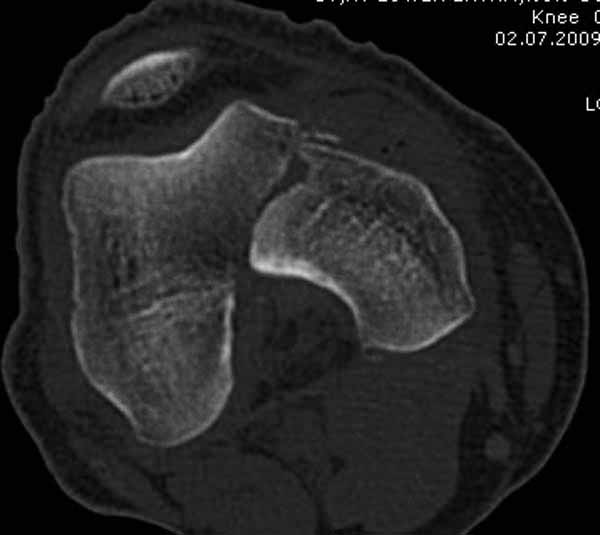

И не обратите, коллега, пока не сделаете четкие анфасные снимки (лучше с дистракцией) где будет четко визуализироваться малоберцовая кость. Думается, что и КТ здесь будет уместно, дабы не пропустить возможное флексионное повреждение (перелом Hoffa).

А теперь по поводу лечения перелома. Среди всех чрез/меж-мыщелковых переломов в 38% сопровождются переломом в корональной плоскости, т.е перелом Hoffa. Nork et al, J Orthop Trauma, 87:564, 2005.

Однако в случае, представленном Константином Никитиным, не может быть применён ни ретроградный ни антеградный остеосинтез. Причина - нереально выполнить вышеуказанные необходимые требования, касающиеся дистальных блокирующих винтов. Из-за низкого перелома латерального мыщелка (перелом Hoffa) невозможно через него провести хотя бы 2 блокирующих винта, поскольку линия перелома мыщелка расположена либо на уровне верхушки межмыщелковой ямки либо незначительно проксимальнее. Поэтому авторам, с моей точки зрения, необходимо прислушаться к рекомендациям Джолдаса.

Рационально ориентироваться на качественный аспект - проблема или решается, или нет. Переломы типа 33C1 или C2 (то есть без фронтального раскалывания мыщелков, как на показанной Вами томограмме) при обычном качестве кости успешно можно фиксировать гвоздями с фронтальными винтами. Получается, их прочностных характеристик уже достаточно.